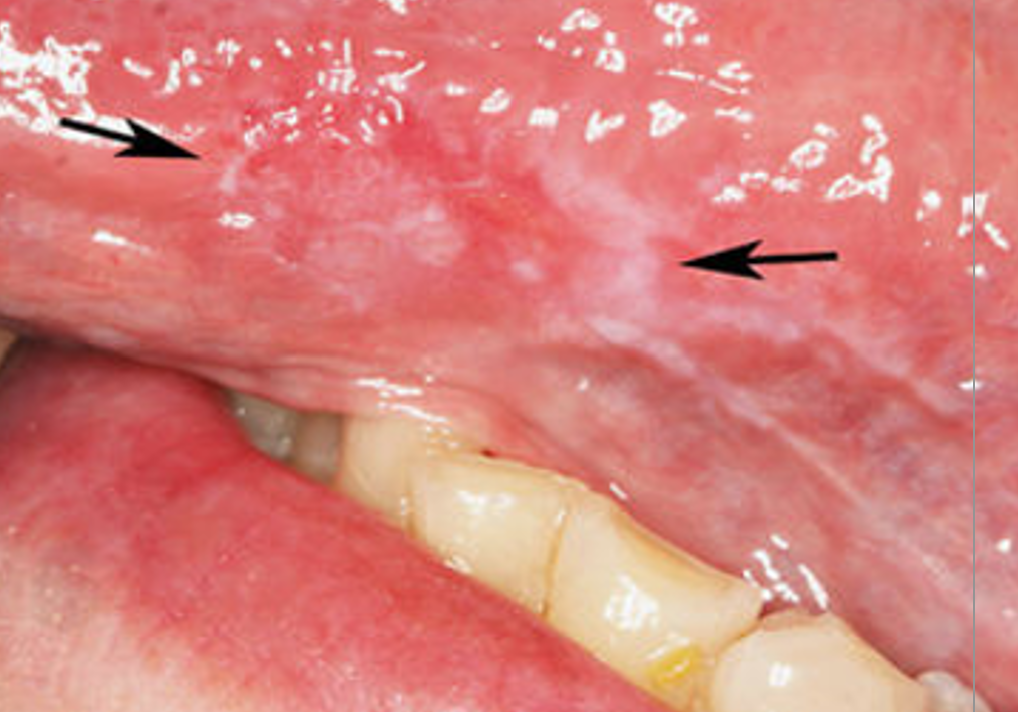

A

Erythroleukoplakia

Q

What questions would you ask this patient to come to a diagnsosis? (5)

• Have you started taking any medications recently?

• (anti-things, NSAIDS, anti-hypertensives)

• Do you have any skin lesions present on your wrists/ankles?

• Do you smoke?

• Does it hurt? If so, what do you take to relieve?

• When did it appear?